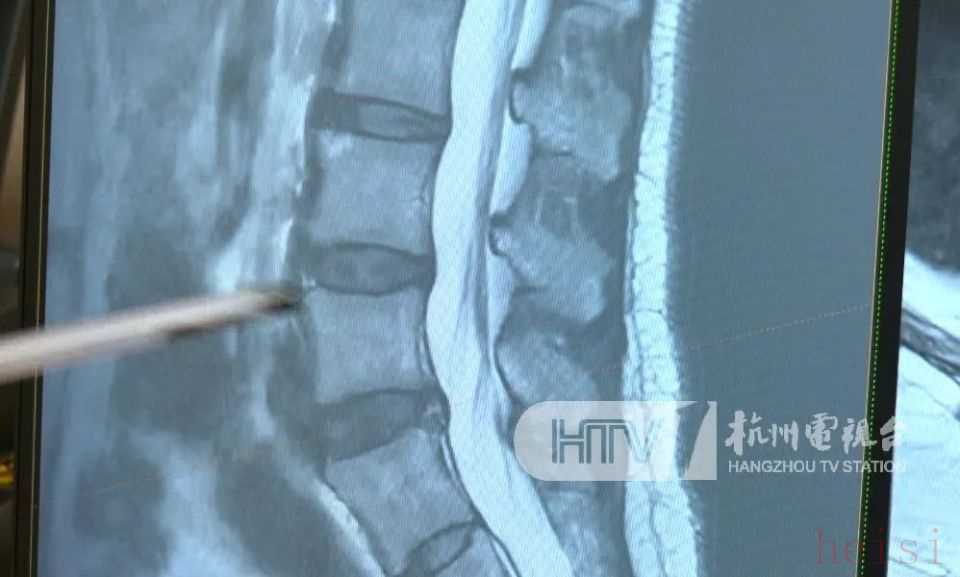

醫(yī)生表示,護(hù)脊書包之所以暢銷,可能和如今中小學(xué)生群體中脊柱側(cè)彎突出這一現(xiàn)象,有很大關(guān)系。

據(jù)統(tǒng)計(jì),我國中小學(xué)生脊柱側(cè)彎發(fā)生率為1%至3%,側(cè)彎人數(shù)超過500萬,并以每年30萬左右的速度遞增。但其實(shí)造成脊柱側(cè)彎的原因多種多樣,除了遺傳因素,和孩子平時(shí)寫作業(yè)時(shí)的坐姿、睡覺姿勢(shì)等,都有關(guān)系。